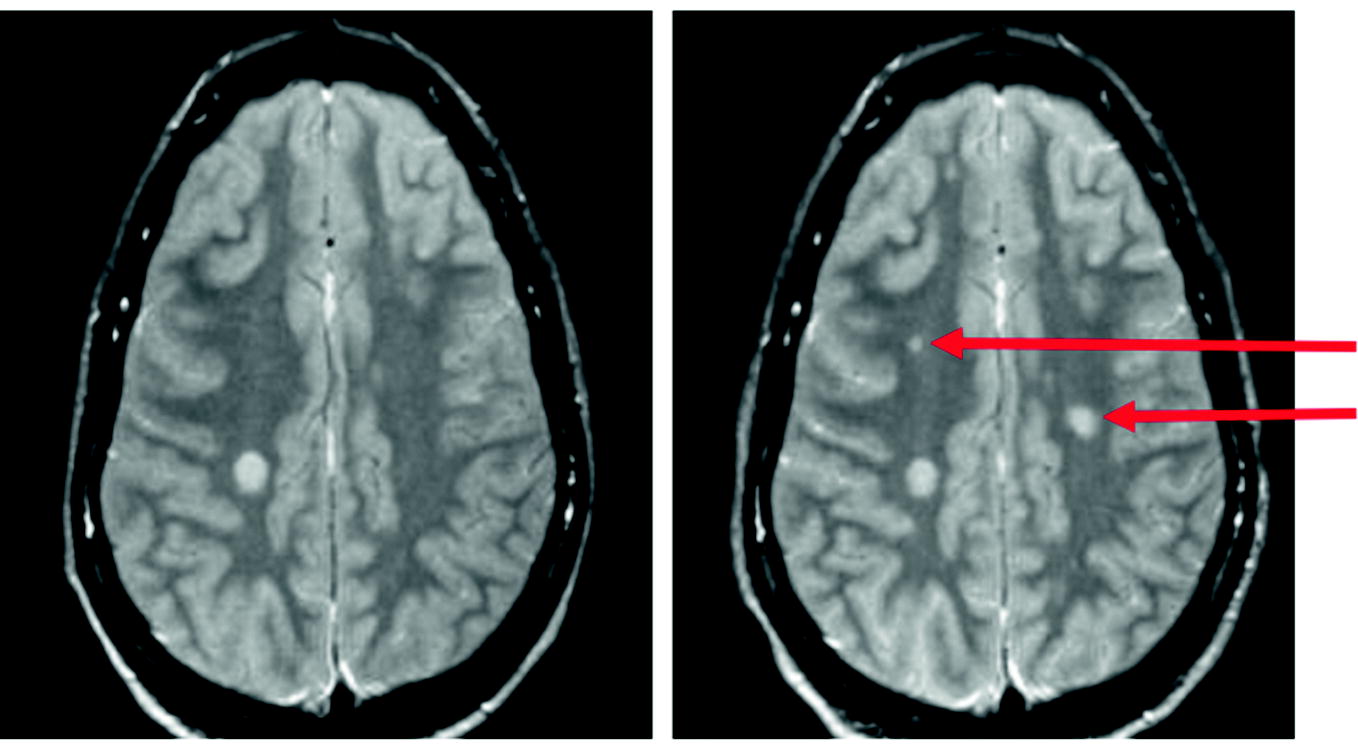

wenn das gehirn weiss wird healthcare in europe com

multiple sklerose kurz und bundig